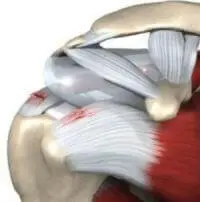

Мышцы ротаторной манжеты (надостная, подостная, подлопаточная и малая круглая) прикрепляются к лопатке и плечевой кости непосредственно вблизи сустава и находятся в глубине, под наружными мышцами плечевого сустава, при этом сухожилие надостной мышцы располагается в субакромиальном пространстве. Обычно между акромионом и сухожильем надостной мышцы достаточно пространства для беспрепятственного скольжения сухожилия при поднятии руки вверх. Также помогает скольжению синовиальная сумка (мешок с жидкостью), расположенная между описанными структурами.

В некоторых случаях объем субакромиального пространства становится недостаточным для движения сухожилия надостной мышцы и развивается субакромиальный синдром (субакромиальный синдром соударения, синдром акромиально-бугоркового конфликта, субакромиальный импинджмент–синдром, impingement syndrome).